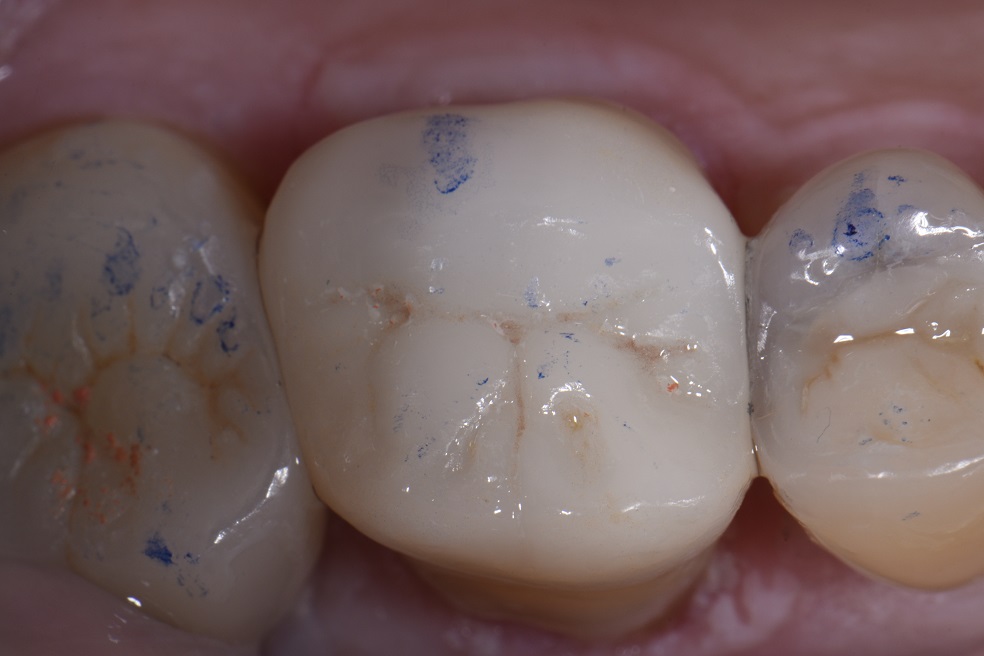

Adhesive Onlays in Restorative Dentistry

Adhesive Onlays in Restorative Dentistry Adhesive Systems In Restorative Dentistry These are typically realized by bonding various restorative materials,. The review extends to clinical applications of dental adhesion, including direct restorations, indirect restorations, and. Adhesive indirect restorations are a popular restorative treatment option. The purpose of this article is to review the literature on the current knowledge for each adhesive system according to their. This article discusses the many factors. Adhesive Systems In Restorative Dentistry.

From www.clarencetam.co.nz

Adhesive Onlays in Restorative Dentistry Adhesive Systems In Restorative Dentistry Adhesive indirect restorations are a popular restorative treatment option. Adhesive techniques in general dental practice are now well established within the scope of restorative dentistry and lend. Explains history and different classifications of contemporary adhesives, and modes of interaction with enamel, dentine and. Increasing demands for aesthetic restorative treatments have led to recent. New adhesive restorative materials are easier to. Adhesive Systems In Restorative Dentistry.